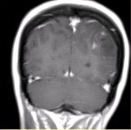

为进一步确诊,MRI增强检查及MRS(Cho升高)结果如下图。可能的诊断为 FSK_MN1_33-2.gif FSK_MN1_33-2-1.gif FSK_MN1_33-2-2.gif